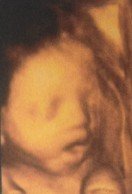

29周宝宝四维彩超,有经验的妈妈们帮我看看男孩女孩 点击展开 郯子怀_TgYm 2020-05-21 06:08 满意回答 好可爱 准爸爸、准妈妈也好可爱。生男生女都一样脂瓣啊阶怠怨 这张图片看不出男司医孩女孩。留作纪念。 渠南风_N2Fy 2020-06-13 20:19 宝宝知道提示您:回答为网友贡献,仅供参考。 为您推荐: 其他回答 如果想妈妈百分之80 是男孩 要是像爸爸百分之80 是女孩 匿名用户 2020-10-06 08:19 就上半身怎能看啊? 匿名用户 2020-08-01 14:58 相关问题 四维彩超回来了帮我看看正常吧,男孩女孩谢谢 请医生帮我看看宝宝发育得好不好,怀孕13周+3天,谢谢! 怀孕24+4周,宝宝怎么动那么多啊,这应该没事吧,还有帮我看看是哪里几个月了